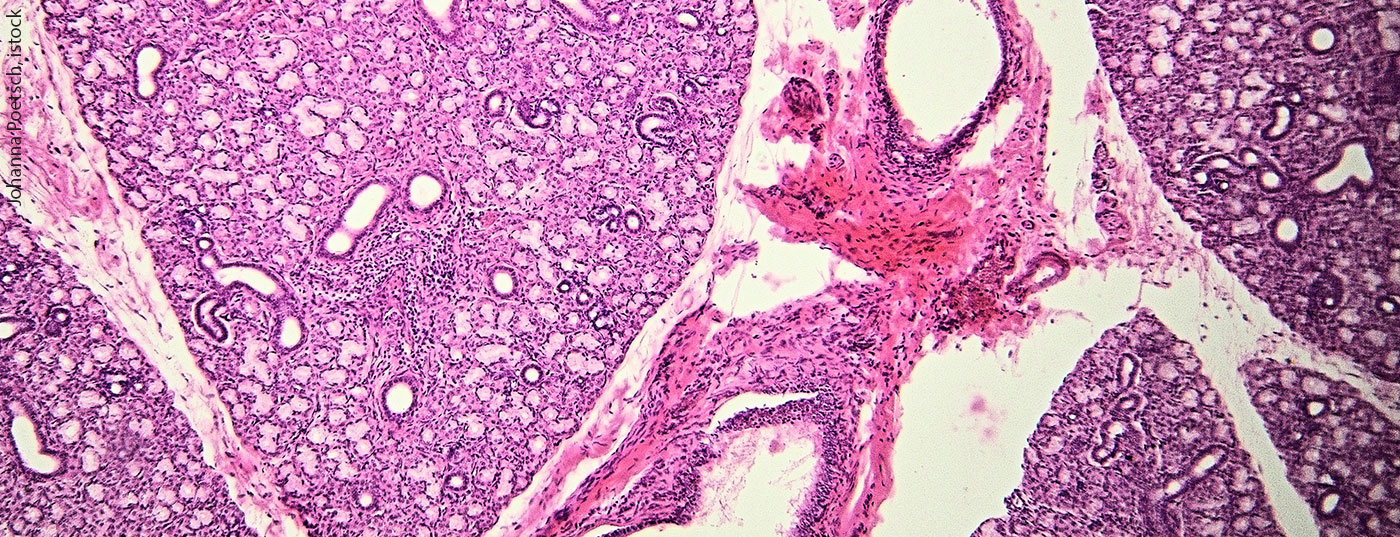

Speicheldrüsenkarzinome: Grundlagen und pharmakologische Interventionen

Speicheldrüsenkarziome sind eine seltene Form maligner Erkrankungen, die Allerdings eine hohe Heterogenität aufweisen. Daher sollte ein molekulares Profiling zur Therapiestratifizierung herangezogen werden. Je nach Subentität können unterschiedliche pharmakologische Interventionen greifen. Dennoch ist aktuell eine chirurgische Intervention nach wie vor Therapie der Wahl.